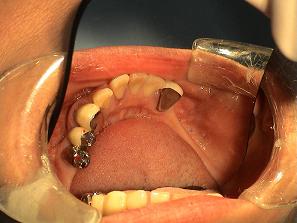

【症例 2】 11歯欠損 (51才,女性)

5歯欠損

正面上(ミラー像)下(ミラー像)

1.

術前のお口の状態です